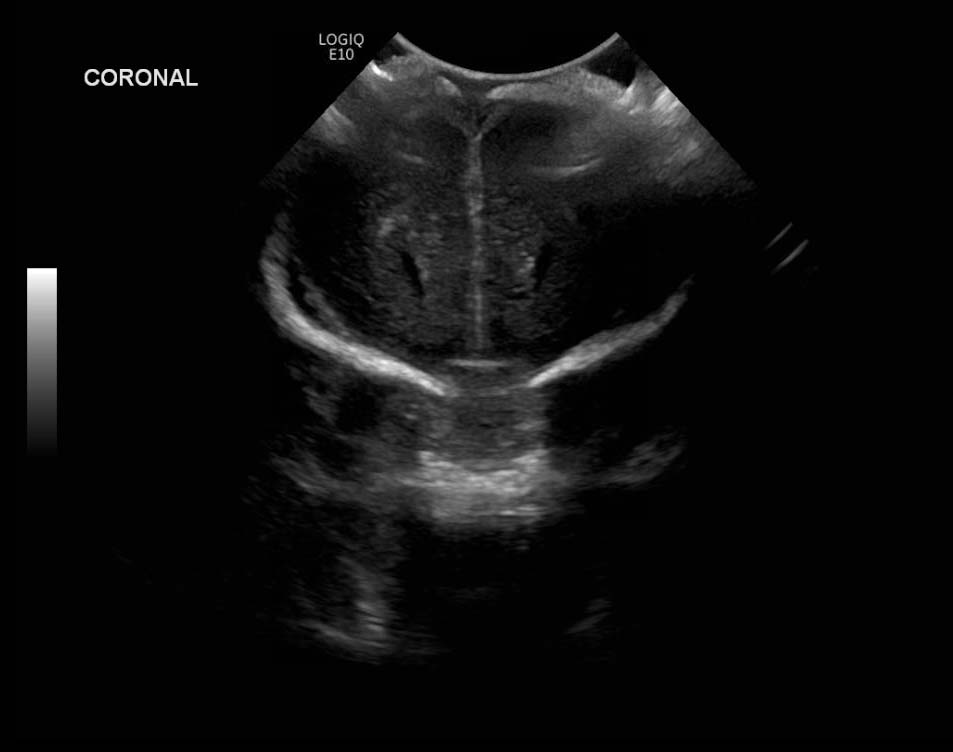

Age: 4 days (born at 24 weeks)

Sex: Male

Indication: Evaluate for germinal matrix hemorrhage

Grade 2 germinal matrix hemorrhage

Sample ReportLeft germinal matrix hemorrhage involving the caudothalamic groove and layering in the occipital horn of the left lateral ventricle without hydrocephalus (grade 2).

No abnormal brain parenchymal echogenicity or extra-axial collections.

Premature sulcation pattern.